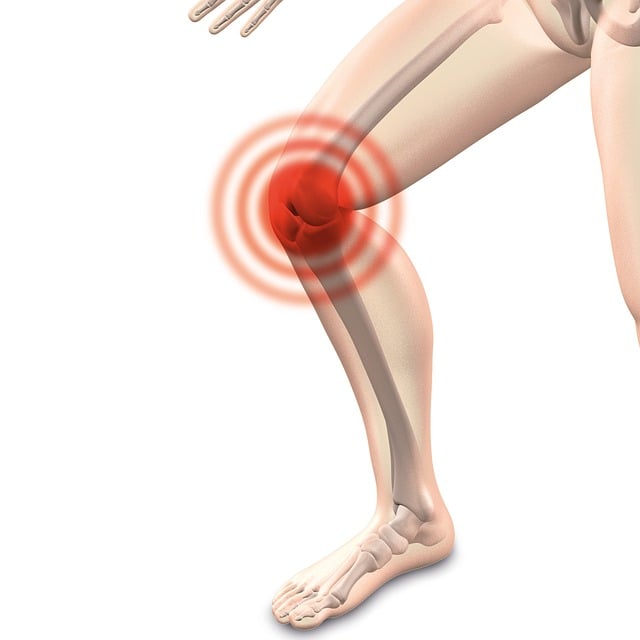

으악! 무릎이야...

오랜만에 운동을 시작하려는데 무릎이 아픈 경험

운동을 꾸준히 해 왔는데, 갑자기 관절이 아픈 경험

이런 경험해보신 적 있으신가요??

그 이유는 바로 "연골 연화증" 때문이라고 합니다.

연골은 뼈 사이의 매끄럽고 탄력 있는 조직으로, 관절을 보호하고 충격을 흡수하는 역할

연골이 손상되면 관절이 염증이나 통증으로 인해 제대로 기능을 하지 못하게 되며,

이로 인해 일상생활에 지장을 줄 수 있습니다.